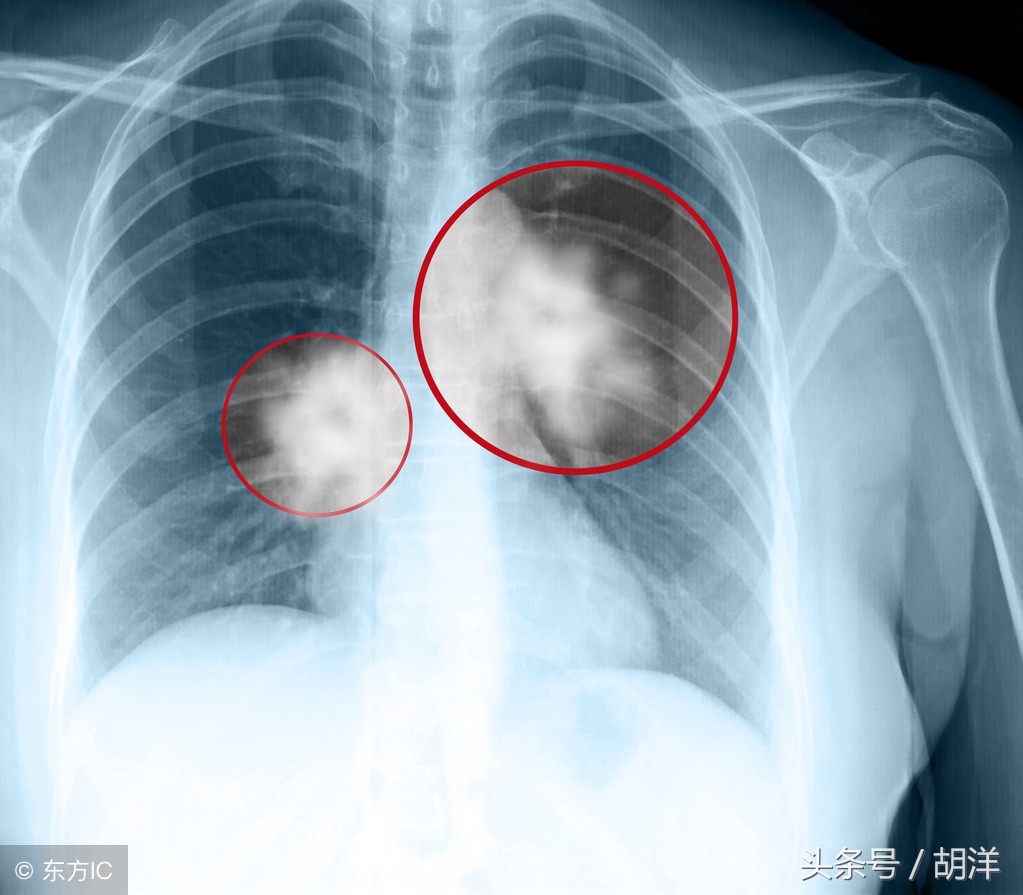

阿来替尼有这么神奇吗?的确,对于基因检测ALK基因阳性的非小细胞肺癌,使用阿来替尼可以极大的延长患者的寿命。在今年6月召开的2018年ASCO年会上,研究人员更新了ALEX研究的结果,这是一个全球多中心的三期临床试验,主要内容为阿来替尼跟一代治疗ALK阳性的靶向药物克唑替尼的对照。在官方公布的数据中,阿来替尼的无进展生存期达到惊人的34.8个月,远远超过了现有标准治疗药物的10.9个月,提高了三倍无进展生存期,且还能有效预防与治疗脑转移。由此可见,阿来替尼无论在有效性还是安全性方面都完胜一代药物克唑替尼。